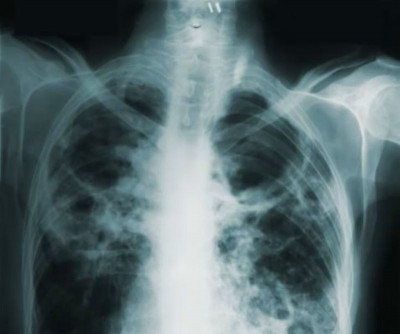

End of Tuberculosis? New tools spark hope of a global breakthrough

The World Health Organization (WHO) called on Tuesday for countries to step up action to end tuberculosis (TB) – one of the world’s deadliest infectious killers – by expanding access to new diagnostic tools that can help save lives.